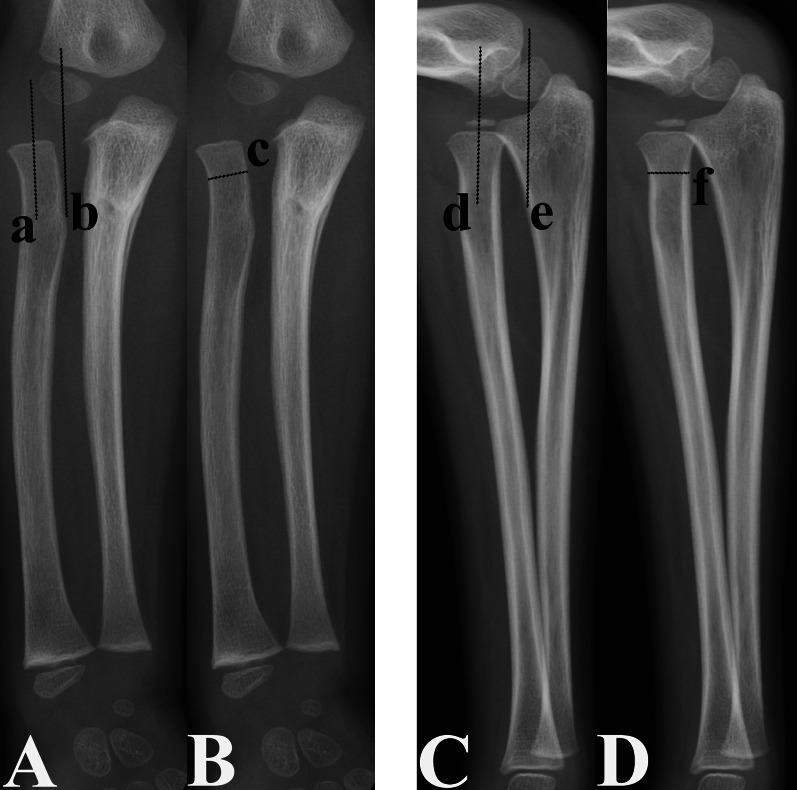

Materials and methods: The clinical data of 142 patients (mean age at the time of injury: 5.73 years) with untreated unilateral CMFs were retrospectively reviewed. The radial neck-shaft angle (RNSAP) and radial head size (RHL) were measured on anteroposterior (AP) and lateral (L) radiographs, respectively. The RHL size was the ratio of the widest width of the proximal radial metaphysis to the narrowest radial neck width. The En-RNSAP and En-RHL were the ratios of the enlargement (En) of the RNSAP angle and RHL size of the injured elbow to those of the uninjured elbow, respectively. Paired-sample t-tests, single-factor analyses and multiple linear regression analyses were performed to evaluate the correlation between the differences in these parameters between the injured and uninjured elbows and the assessed risk factors. These risk factors included institution, sex, laterality, age at injury, time from injury to diagnosis, direction of RH dislocation, distance of RH dislocation (DD-RH), presence of radial or median nerve injury, heterotopic ossification and immobilization of the elbow after injury.